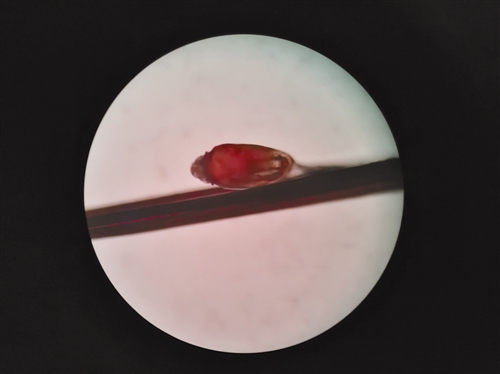

给童童看病的,是玉环市人民医院眼科主任王建君。她在裂隙灯下仔细查看,发现孩子的双眼局部红肿明显,睫毛根部密密麻麻长着一层白色的颗粒,类似虫卵。王建君赶紧取“标本”,并送到了检验科。

一开始,王建君判断这些白色颗粒是螨虫之类的寄生虫,但放到检验科的显微镜下一看,居然是活的虱子。睫毛上长虱子!王建君说自己从医28年来,还是第一次接诊这样的病例。

之后,王建君在眼科显微镜下,将童童两眼睫毛全部剪除,清理睫毛根部皮肤,消毒、用药,并叮嘱其妈妈两天后再带来复查,以防虱子没取干净或再次寄生。